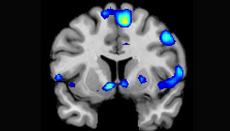

¿Dios en el cerebro? La experiencia religiosa desde la neurociencia

La Neurociencia se puede plantear estudiar la experiencia religiosa; este enfoque puede interesar también mucho a la Teología. Ambas líneas abren un campo de estudio interdisciplinar que permite reflexionar sobre la Teología en relación con las ciencias y como exigencia del pensamiento.